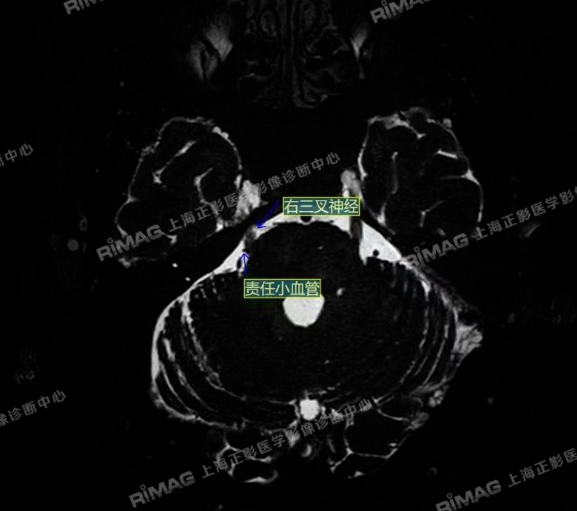

本例患者接受了MRTA(磁共振体层成像脑血管显影术)检查。这是一种非常精细的磁共振成像技术,能够清晰显示脑神经与周围血管的立体关系,尤其适用于三叉神经痛的病因诊断。

影像表现:右侧三叉神经根部外下方见小血管斜跨,与三叉神经分界不清;左侧未见明显异常(对照)。

影像图上,血管与神经的纠缠一目了然。这正是现代影像学的魅力——它不仅是“拍片子”,更是“讲故事”,是把病人多年的痛苦,转化为可视化的医学证据。